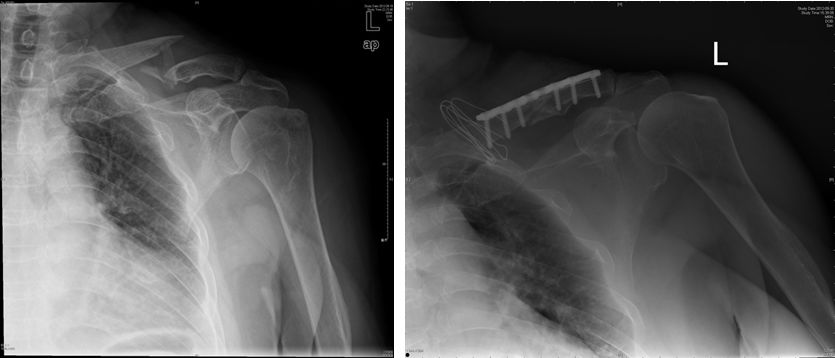

3、尺桡骨骨折

功能锻炼方法:

固定后即可做伸屈指、掌、腕关节活动,患肢做主动肌肉收缩活动。

肩、肘关节的活动同肱骨干骨折。骨折愈合后的锻炼:骨折愈合后,增加前臂旋转活动及用手推墙动作,使上、下骨折端产生纵轴挤压力。